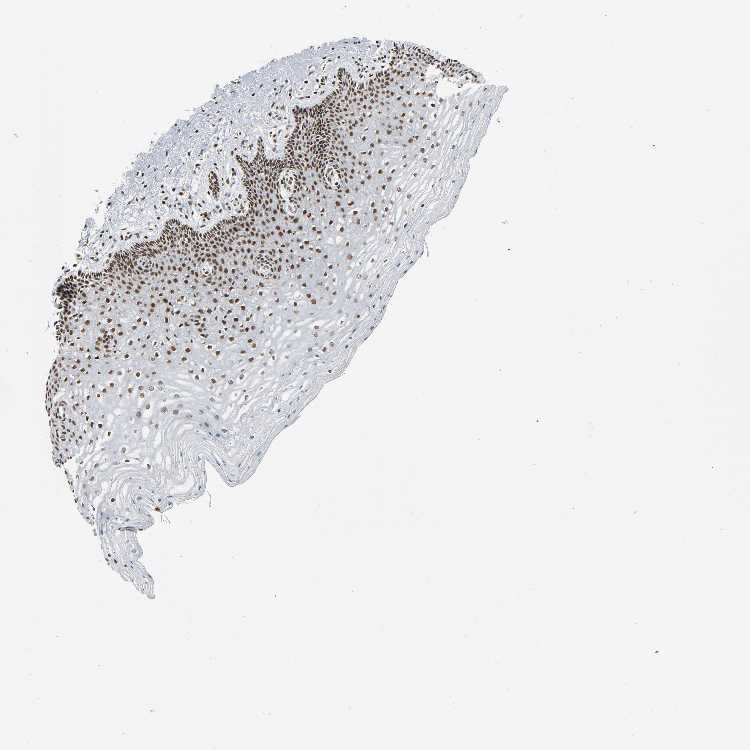

CERVIX - Antibody stainingi

Antibody staining in the annotated cell types in the current human tissue is reported as not detected, low, medium, or high, based on conventional immunohistochemistry profiling in selected tissues. This score is based on the combination of the staining intensity and fraction of stained cells.

Each image is clickable and will lead to virtual microscopy that enables deeper exploration of all samples and also displays staining intensity scores, fraction scores and subcellular localization as well as patient and tissue information for each sample.

Antibody HPA006738Antibody CAB004216

Glandular cells HighHigh

Squamous epithelial cells HighHigh